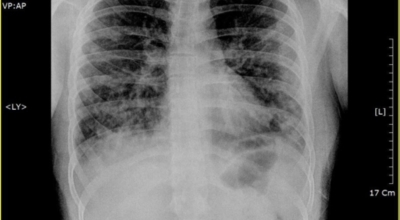

폐렴은 증상만으로는 정확하게 진단하기 어려우므로, 다음과 같은 검사를 통해 진단합니다.

- 흉부 X선 촬영: 폐의 염증 부위를 확인하는 가장 기본적인 검사입니다.

- CT 촬영: X선 촬영보다 더 자세한 영상을 얻을 수 있어 폐렴의 위치와 범위를 정확하게 파악할 수 있습니다.